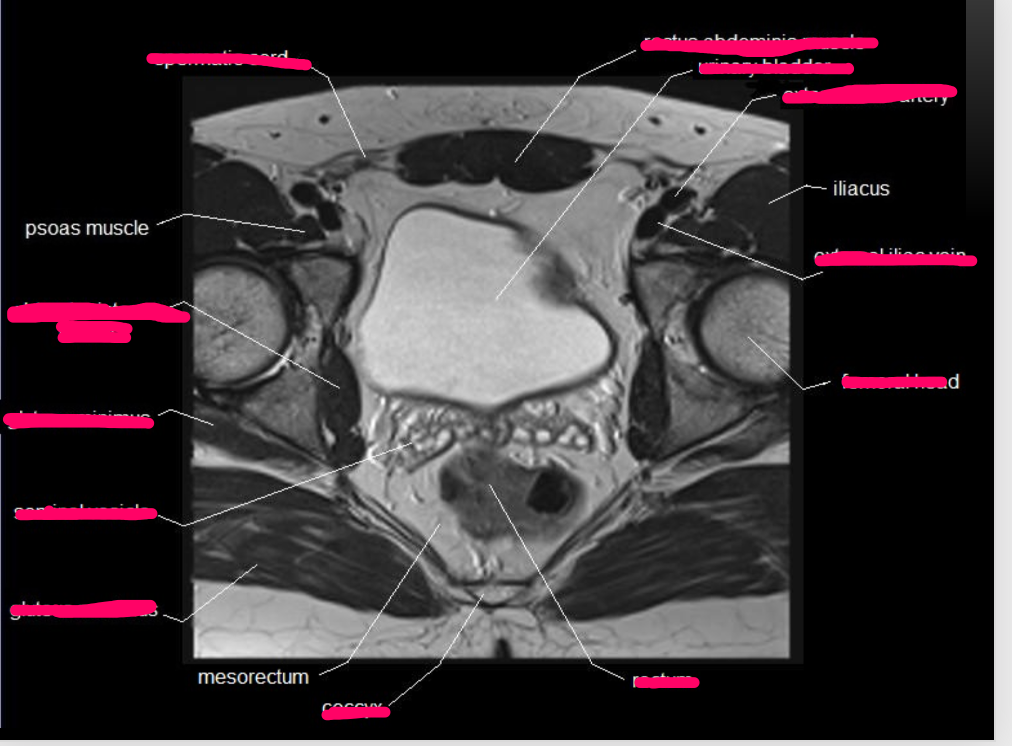

What type of imaging modality is this & fill in the blanks

MRI prostate, axial